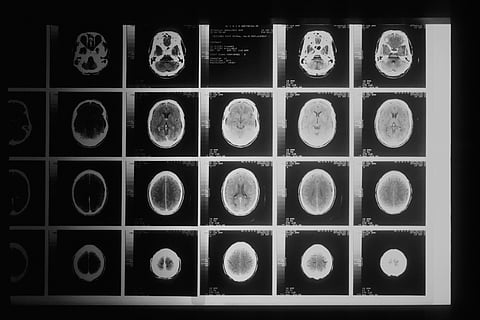

"Over a series of MRI scans, I watched as the tumour completely disappeared," Grill told AFP.

Seven other children in the trial survived years after being diagnosed, but only Lucas's tumour completely vanished.